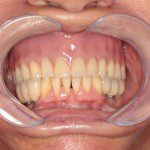

- Depois

- Sorriso final